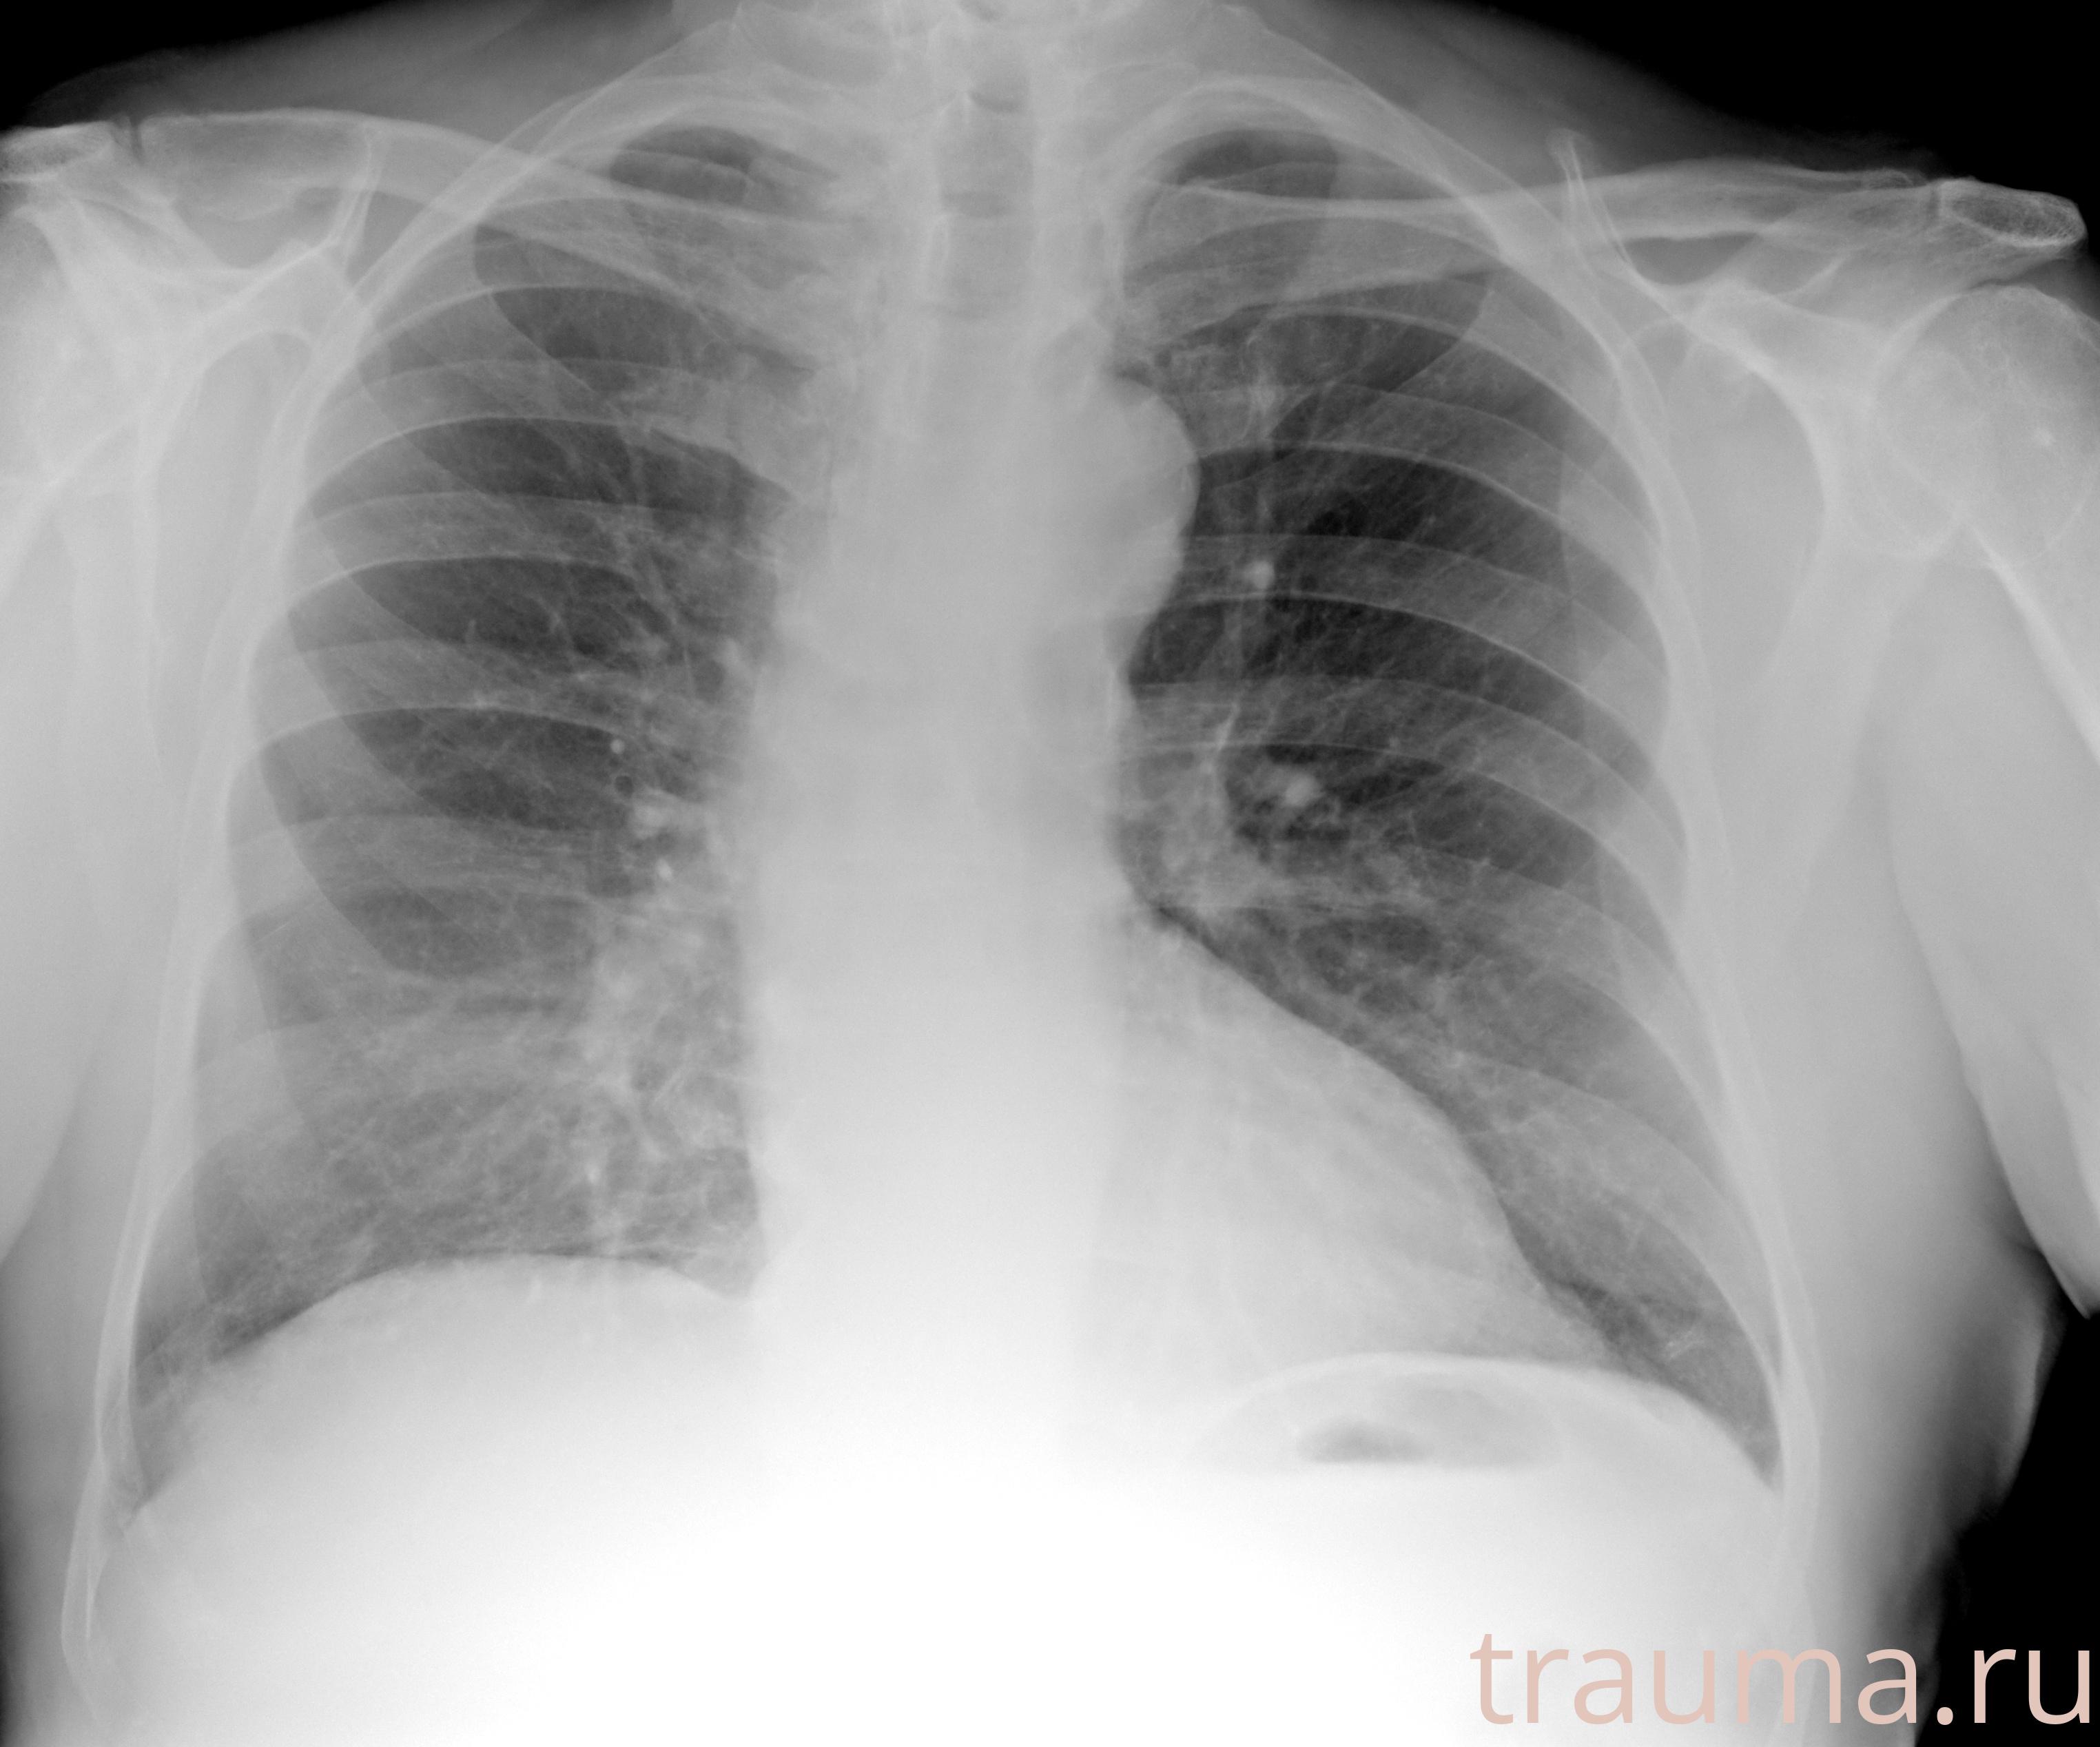

Рентгенограммы

Рентген на дому: по вашему адресу приезжает врач-рентгенолог, травматолог-ортопед с мобильным рентгеновским аппаратом, проводит диагностику травмы или заболевания, делает необходимые рентгенограммы, дает рекомендации по дальнейшему лечению. Получить качественные снимки в домашних условиях возможно благодаря уникальной методике, разработанной МосРентген Центром для института  Склифосовского

при переломе шейки бедра и пневмонии от компании МосРентген Центр - партнера Института имени Склифосовского